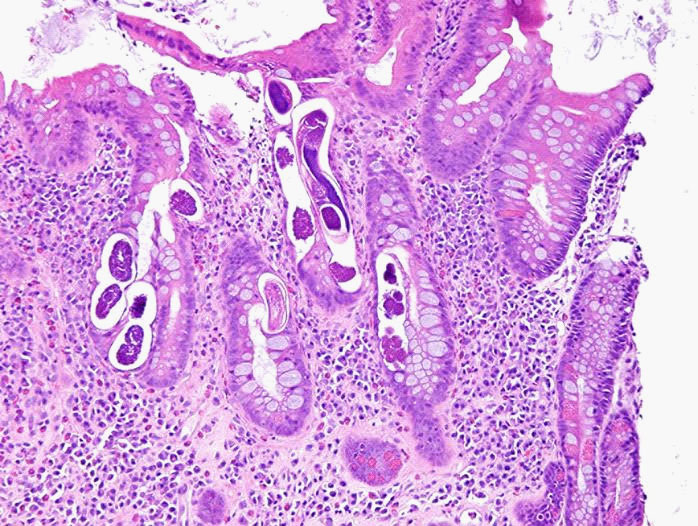

The pathology revealed worms suggestive of Strongyloides (see Figure 2). Upon further questioning, the patient was born in the Dominican Republic and moved to the United States more than 10 years ago but he denied history of recent travel. The patient was started on ivermectin which was then switched to praziquantel given concern of inadequate absorption due to ileus. The patient clinically improved with cessation of bleeding. A subsequent ERCP was performed to rule out biliary obstruction which was normal, and his liver chemistries significantly improved. He was discharged to complete a 14-day course of praziquantel from his first negative ova and parasite stool exam.

Strongyloides colitis can sometimes mimic ulcerative colitis, but distinctive features of the strongyloidiasis include skip pattern of the inflammation, distal attenuation of the disease, eosinophil-rich infiltrates, relatively intact crypt architecture, and frequent involvement of submucosa [5].